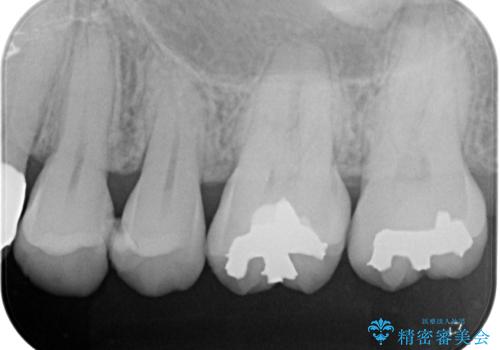

- 当院で矯正終了後、歯に穴が開いてフロスが引っかかるとのことでセラミックで修復することになった患者様です。

虫歯がないか確認し、セラミックインレーにて修復することになりました。

セラミックインレー装着時には、唾液の侵入を防ぐために、ラバーダム防湿を行いました。